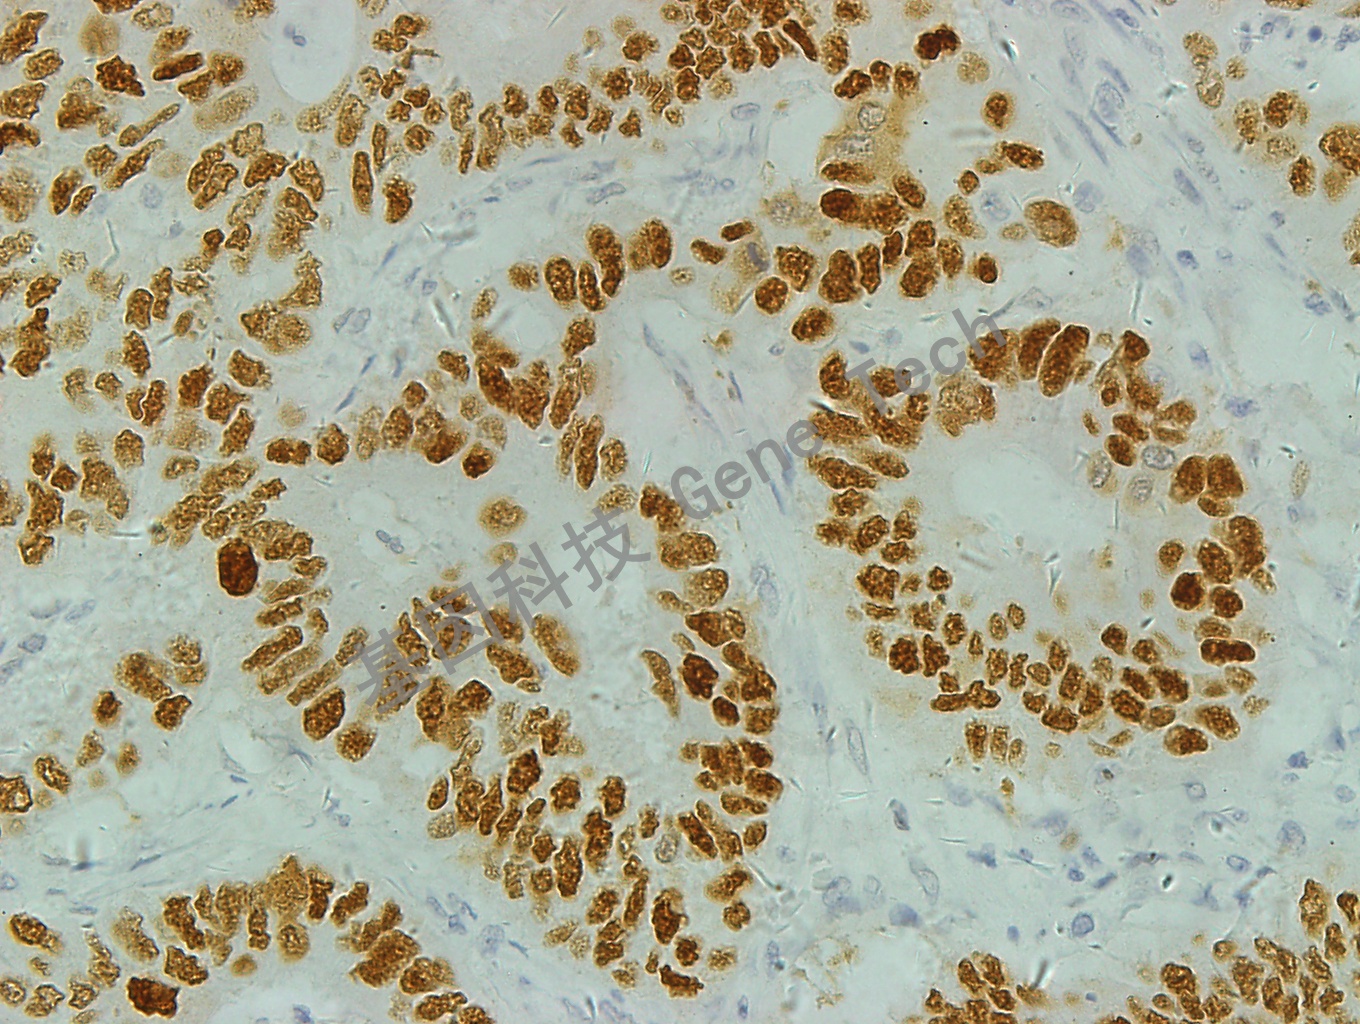

结肠癌石蜡切片,用 p53(GT2095)染色,细胞核着色,DAB 显色。